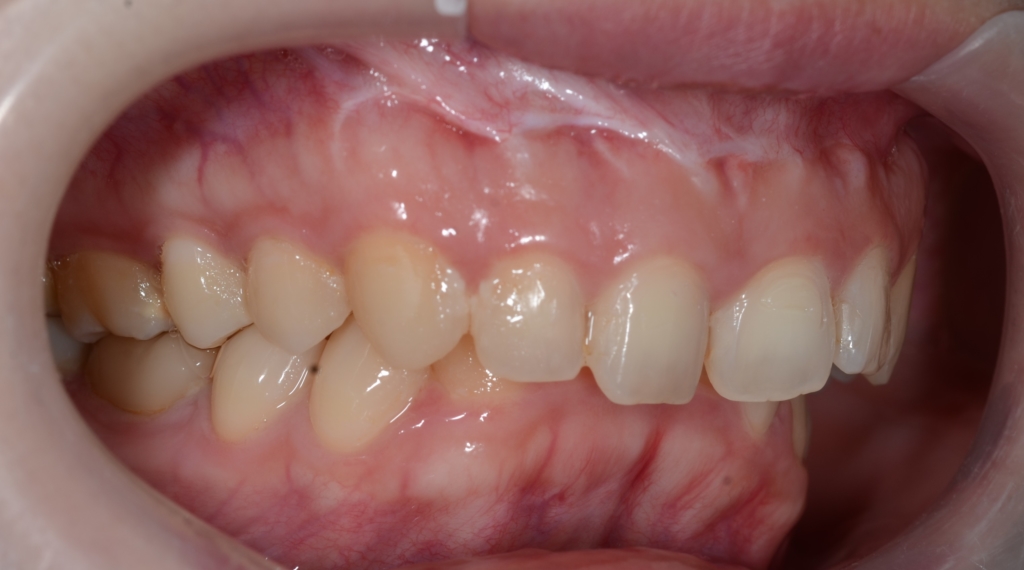

【Before】

【治療方針】

1.アンカースクリューを用いて、上顎前歯を圧下させてガミースマイルの改善を図る

2.その後、抜歯をしてスペースを確保して、上の前歯を最大限に引っ込める

という治療計画にて、矯正を進めることにしました。

【抜歯】

上の左右の奥歯を1本ずつ計2本抜歯(前から4番目の第一小臼歯です)

下は非抜歯です